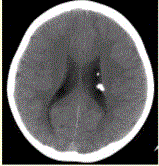

问题 患者男,20岁,面部皮脂腺瘤,头CT显示如下图。 可能的诊断是

选项 A.少枝胶质细胞瘤 B.星形细胞瘤 C.结节性硬化 D.陈旧性血肿 E.颅面血管瘤病(Sturge-Weber)综合征

答案 C